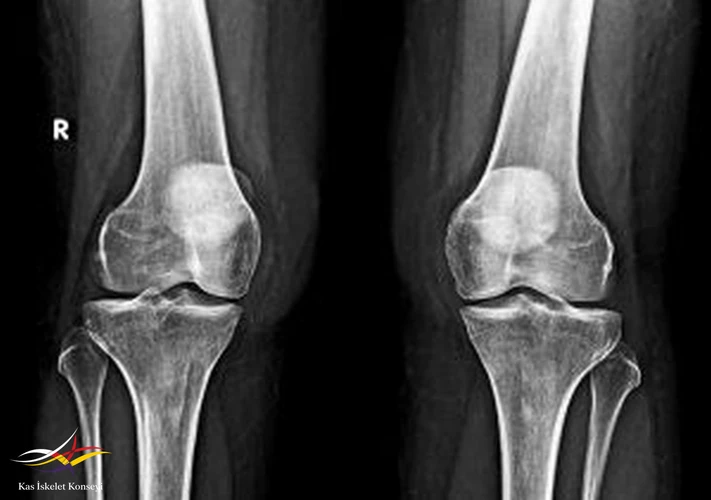

İncelemeler: MRG: Sağ dizde valgus deformitesi, bursit, cilt altı ödemle uyumlu. AFR'ler normal düzeyde.

Resim 1. Direkt diz grafisi.